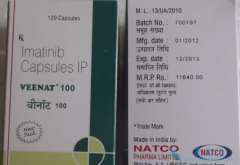

格列卫( 伊马替尼 )用于治疗治疗慢性粒细胞白血病和胃肠间质瘤的靶向药物。格列卫(伊马替尼)因为在中国价格高昂,即使有些地方已经纳入医保,但是比较下印度版的格列卫(伊马替尼)还是毫不犹豫的选择了印度版,为什么呢?印度版格列卫(伊马替尼) ...

我们知道瑞士诺华格列卫(伊马替尼)的价格一个月要两万多,但是 印度格列卫 (伊马替尼)的价格一个月竟然连一千都不需要,很多会问两个版本的格列卫(伊马替尼)价格差别这么大,效果是不是一样呢?如果遇到什么问题,可以先联系康安途海外就医的专业 ...

格列卫( 伊马替尼 )是慢粒白血病和胃肠道间质瘤用药,不只效果好,而且耐药期长,有很多患者服用格列卫(伊马替尼)长达五年以上,有的甚至十年,但是这些患者里边绝大部分都是用的印度版的格列卫(伊马替尼),为什么呢?话说格列卫(伊马替尼)无论 ...

为什么 印度格列卫 (伊马替尼)能这么便宜?原研药格列卫(伊马替尼)的研发往往需要十几年的时间以及庞大的资金投入,新药研发出来后,成本自然转嫁到药价之上。原研药的专利保护期一般是20年,专利保护到期之后,药企便可以进行仿制。在专利保护期间 ...